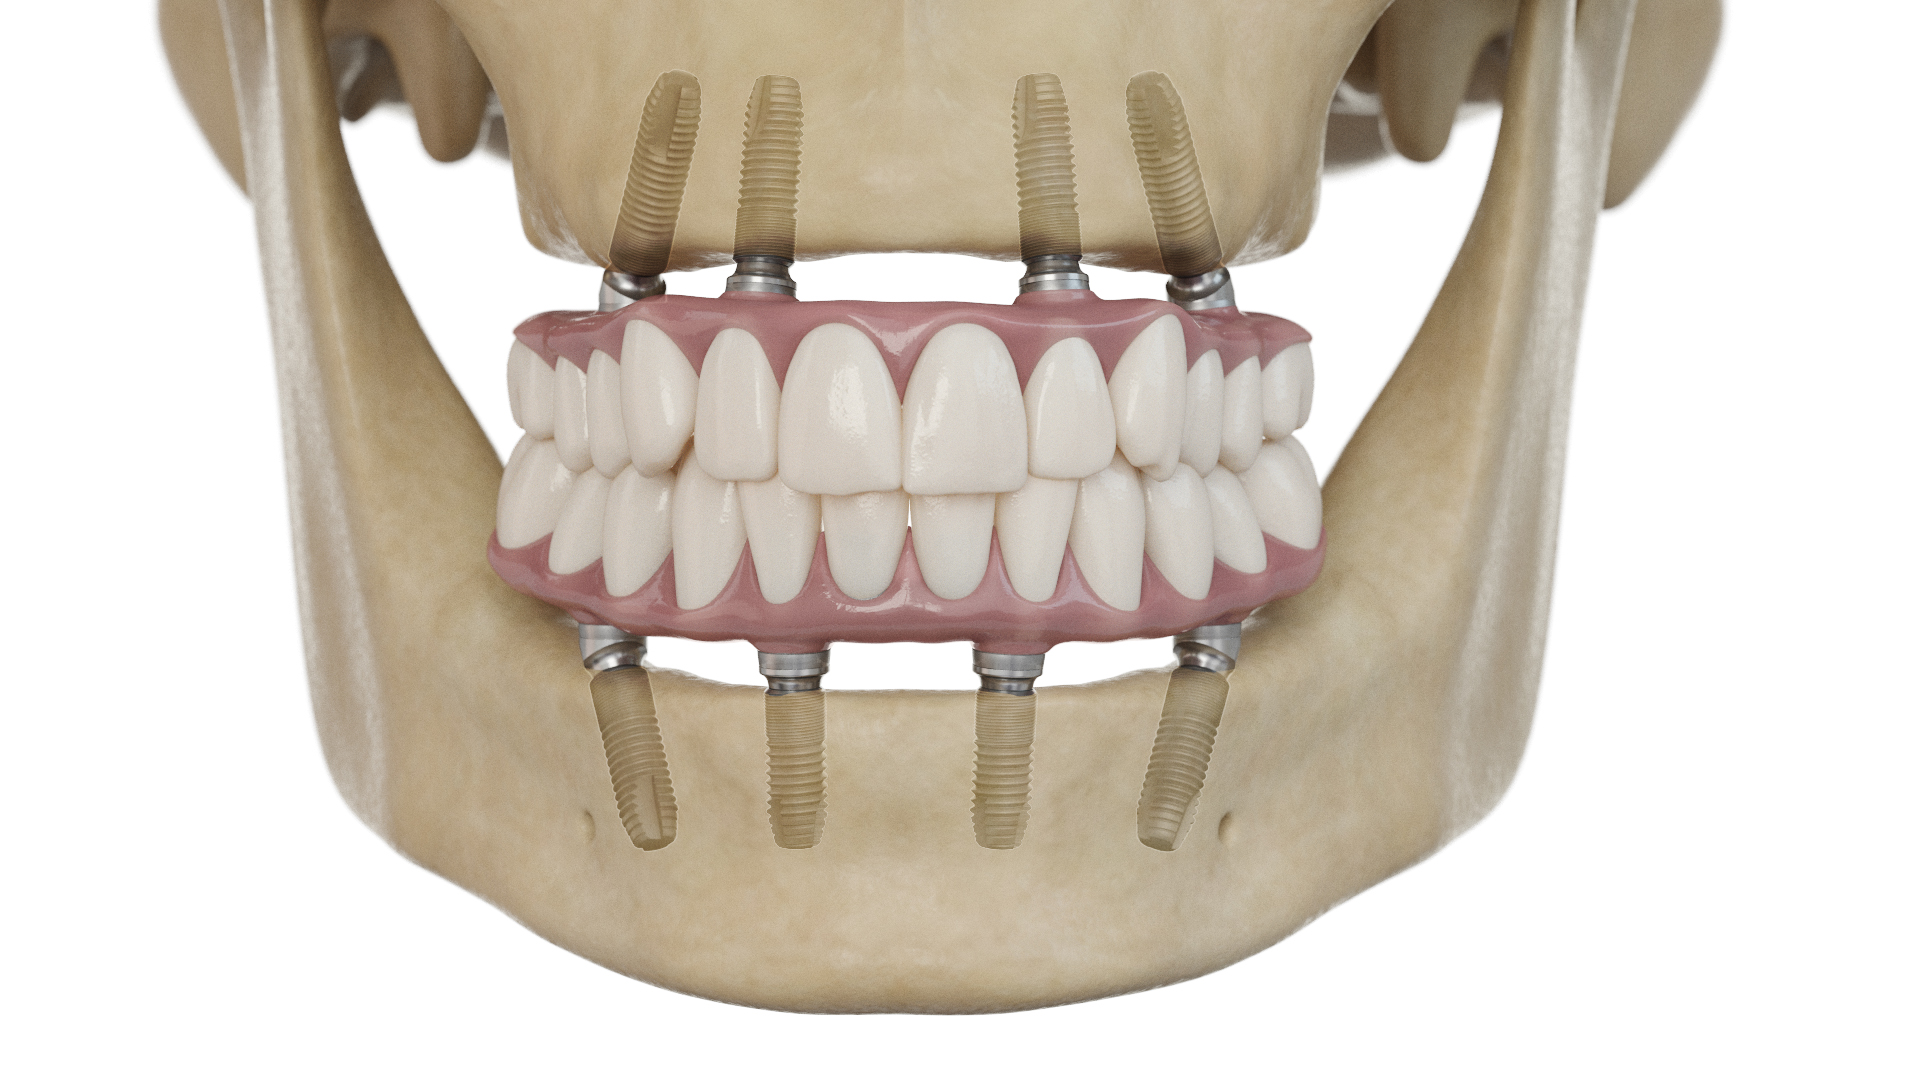

SmartFix EV_1234277 alternate text for this image

The implant treatment process contains many steps—from imaging and diagnosis, treatment planning and implant surgery to abutment selection, restorative solutions and patient follow-up. Dentsply Sirona Implants presents several new solutions to their already extensive portfolio to delegates at their second World Summit Tour stop in San Diego. “Whether thought leader, researcher, educator, Specialist, GP, or … Read more